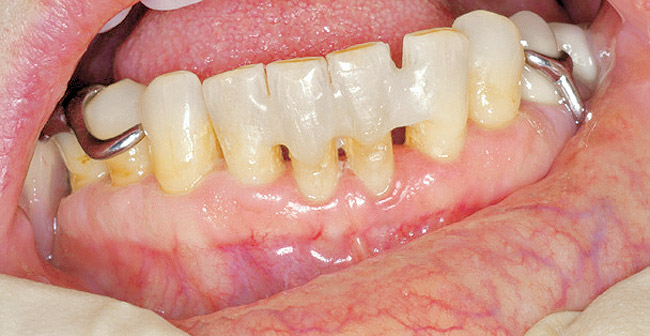

Figure 1  Exposed bone in the mandibular jaw that is characteristic of BRONJ. Photo courtesy of Robert Marx, DDS.

Figure 1

Bisphosphonate-related osteonecrosis of the jaws (BRONJ) is characterized by the presence of exposed bone in the oral cavity for more than 8 weeks in a patient who has been taking bisphosphonates and who has not had any radiation therapy in the oral cavity3 (Figure 1). The risk of BRONJ from the use of oral bisphosphonates is very low, currently about 1%.8 Most researchers believe this incidence is so low because it takes many years for the drug to saturate the bone. Most cases of BRONJ from oral bisphosphonates occur after at least 3 years of drug use.9 However, a recent study by Cartsos et al of over 700,000 medical claims found no increased incidence of inflammatory conditions, including osteonecrosis.10